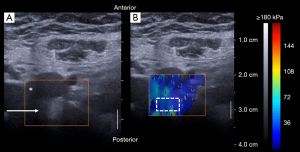

After assessment of the L3/4 anterior fusion by a CT-scan at 1 year, the L5 posterior fixation was removed. The patient had not undergone rehabilitation with physiotherapy. Ultrasound elastography of the anterior annulus fibrosus were performed according to an already validated protocol (9,11) (Figure 2). Shear Wave Speed (SWS) was measured in the anterior part of the annulus fibrosus of L4/5 and L5S1 discs. Three clips of about 10 s (about 10 elastography frames per clip) were recorded for each disc, i.e., L4/5 and L5/S1. The average SWS value was calculated in each region of interest to obtain a single SWS value (from three clips × 10 frames = 30 frames per disc) for L4/5 and L5/S1. The size of the region of interest (ROI) was also adapted to the disc and to the elastographic signal, to avoid signal saturation or missing signal. ROI was between 1 and 3 cm2. Acquisitions were performed, by the same operator, one year after fracture treatment (before L5 fixation removal), then 6 months and 1 year after L5 fixation removal. Frontal and lateral X-rays were also acquired at each time point of the treatment. Dynamic flexion-extension bending films were done 1 year after L5 fixation removal. Two years after L5 fixation removal, the patient was symptoms-free and had a normal function. Dynamic X-rays showed a restoration of disc mobility at the L4/5 level without signs of instability or disc degeneration (Figure 1). Although SWS was within the normality corridor before removal of L5 fixation, it decreased at 6 months and 1 year after L5 fixation removal (Figure 3).

To perform the procedure, the adolescent should be relaxed, and constant pressure should be applied to the probe to clear the bowel contents and gas. It is advisable to first detect the aortic bifurcation, which corresponds to the L4 vertebra in 64% of subjects (12). Then the probe can slide caudally, to measure L4/5 and L5/S1. The lamellar structure of the annulus fibrosus is only visible if the probe is in the same plane as the disc. The learning curve for in vivo annulus fibrosus imaging is not long, but care must be taken to obtain stable and good quality images. A limitation of the technique is that the measurement is only of the anterior part of the annulus fibrosus in the lumbar region. The thoracic cage does not allow us to carry out measurements above L2. The measurements were carried out by the same operator, however there may be intra-operator variations. The feasibility study describing the protocol used in this case found an intra-operator repeatability of 5.0% and an intra-class correlation coefficient greater than 0.9 for each operator (11).